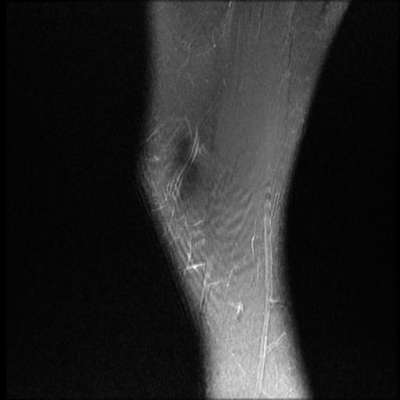

图1展示了MBSMFFPN模型在股骨MRI图像上的检测结果。从图中可以看出,模型能够准确识别和定位股骨的各个关键结构,包括骨髓腔、皮质骨和周围软组织。特别值得注意的是,对于边界模糊的小目标(如早期骨髓腔病变),MBSMFFPN模型表现出色,这得益于多尺度特征融合机制和改进的检测头设计。